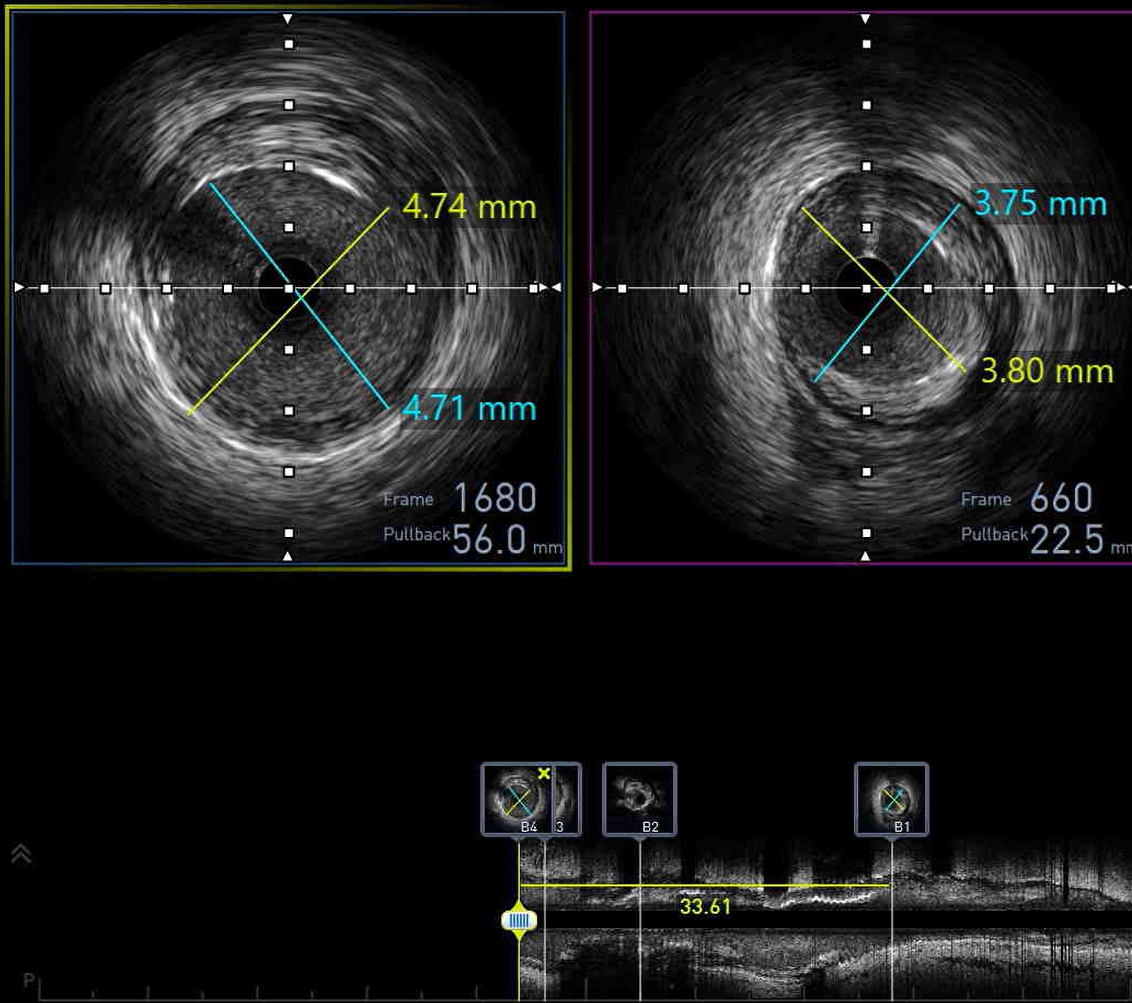

Several investigations were performed to prepare the 67-year-old patient for repeat coronary angiography, with plan for DCB or PCI if required. The team carefully reviewed her clinical stability, cardiac enzymes and imaging results to decide the safest path forward. Each step reflected both urgency and hope to restore her coronary flow and prevent another critical cardiac event from threatening her recovery.

The patient underwent coronary angiography, where the team attempted to reopen the previously stented proximal mid LAD that had become occluded. After multiple revascularization efforts from ballooning to placing a ne DES in the mid LAD. A type III perforation occurred in the distal LAD during balloon inflation. Despite immediate measures including balloon tamponade and covered stent deployment, the perforation remained visible on follow-up angiography.